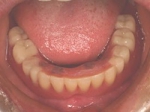

片側2歯欠損 主訴-入れ歯を使ってみたが違和感強くてダメ。固定のものにしたい。術前下顎口腔内(鏡像)